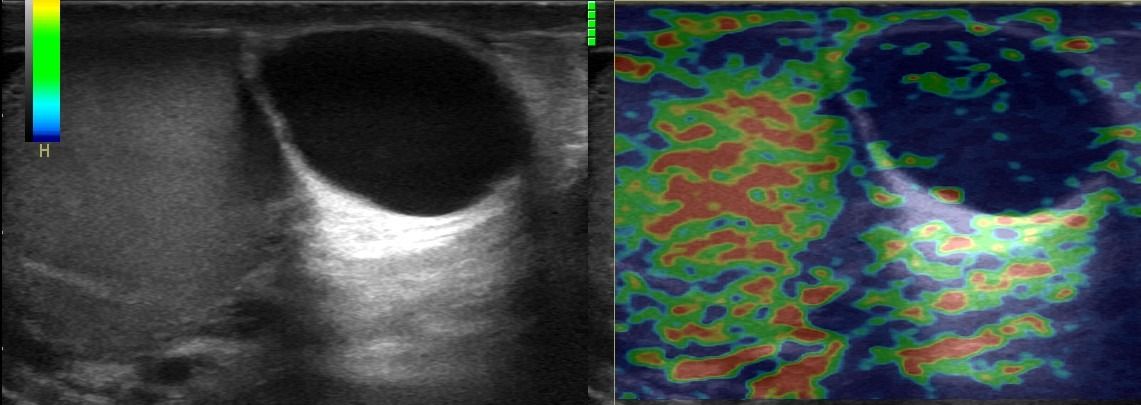

Εξειδικευμένες Υπερηχογραφικές Τεχνικές

Η μελέτη με Έγχρωμο Doppler παρέχει κρίσιμες πληροφορίες σχετικά με την αγγείωση των όρχεων, ανιχνεύοντας αποκλεισμούς συστροφής ή φλεγμονές, όπως η ορχίτιδα.

Η εμπειρία του εξειδικευμένου Ιατρού-Ακτινολόγου σε συνδυασμό με τις προηγμένες διαγνωστικές δυνατότητες των υπερήχων εξασφαλίζουν την ακριβή διάγνωση και αξιολόγηση των παθήσεων και βλαβών των όρχεων.